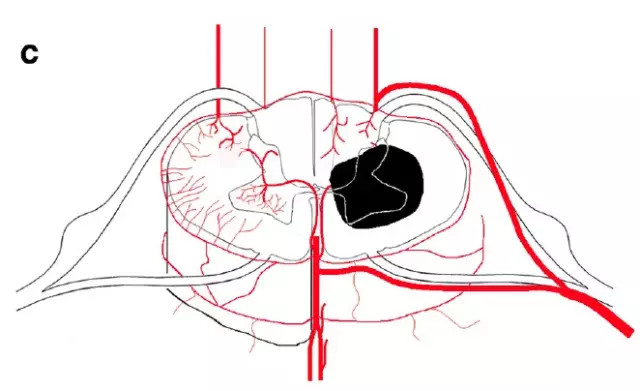

图c,脊髓沟动脉分布区梗死

图f,脊髓前角内外系统之间的分水岭区梗死(蛇眼征)